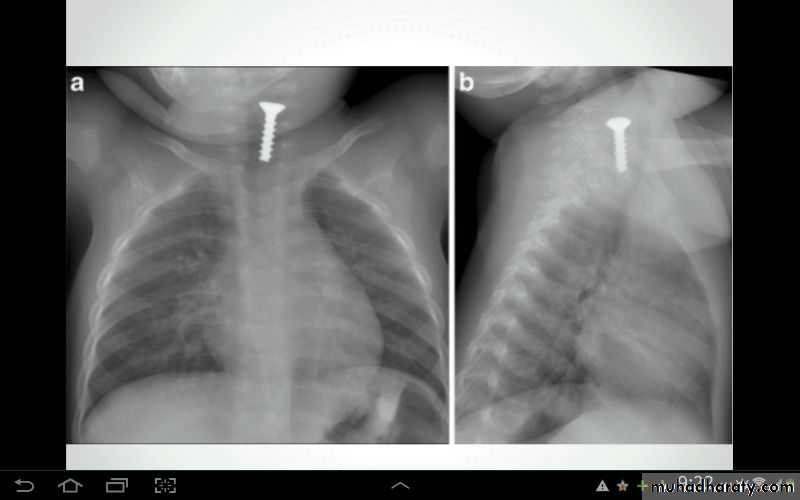

• Malposition